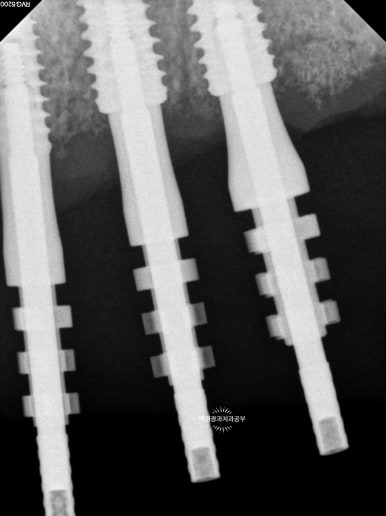

약 1달 뒤 아래턱뼈 남은 치아의 발치와 함께 임플란트 1차 수술을 시행하였습니다.

아래턱 임플란트 1차수술 후

앞서 말씀드렸듯이 일반적으로 아래턱뼈에 심어진 임플란트의 치유기간이 위턱뼈에 심어진 임플란트의 치유기간 보다 1달정도 적은 시간을 갖게 됩니다.

이에 따라 아래턱뼈 수술을 1달 정도 뒤에 하게 되었어요.

물론 환자분도 꽤나 힘든 수술이기에 1달 정도의 여유를 갖고 싶어 하셨거든요.

혹시 눈치채셨나요?

발치 즉시임플란트의 경우 이를 뽑고 바로 임플란트 수술을 시행하기 때문에, 전체 치료기간을 꽤나 줄일 수 있는 장점이 있습니다.!! 다만, 모든 경우에 가능하다고 할 수는 없고 보통은 이를 뽑고 1달쯤 뒤에 잇몸이 회복되면 임플란트 1차수술을 시행합니다.

즉, 이를 뽑고 1달 임플란트를 심고 3달 총 4달의 시간은 지나야 비로소 임플란트 머리를 제작해 드릴 수 있다는 말씀!